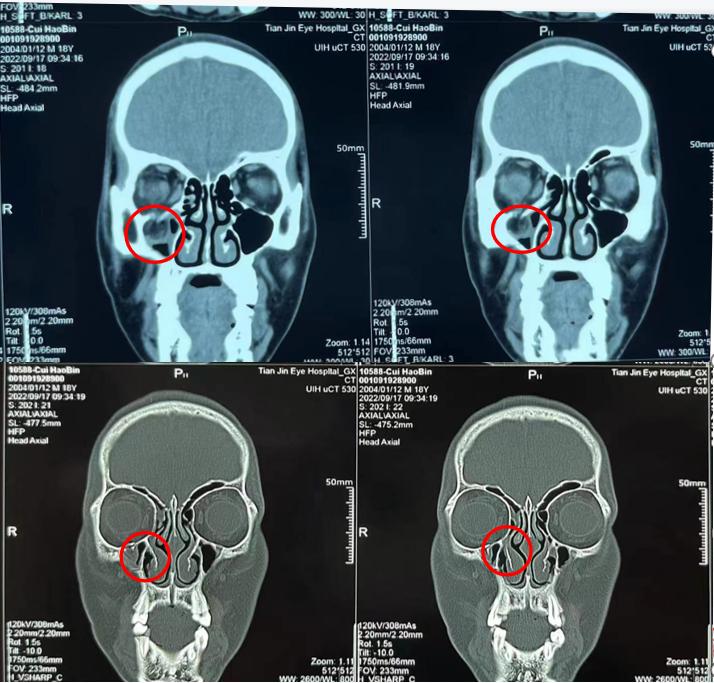

CT:右眼眶下壁骨质连续性中断,下直肌部分眶脂肪突向临近上颌窦,右眼下直肌嵌于骨折缝隙,肌肉变形增粗。右侧眼睑部软组织肿胀。

诊断:1. 眶壁骨折。2. 右眼非共同性斜视。3. 右眼眶下神经损伤。